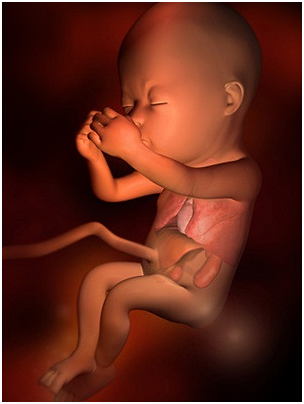

怀孕第28周胎儿图 从现在开始,你就进入了孕晚期,要注意的事情很多呦!你要每天做胎动...

怀孕第28周胎儿图 从现在开始,你就进入了孕晚期,要注意的事情很多呦!你要每天做胎动... -